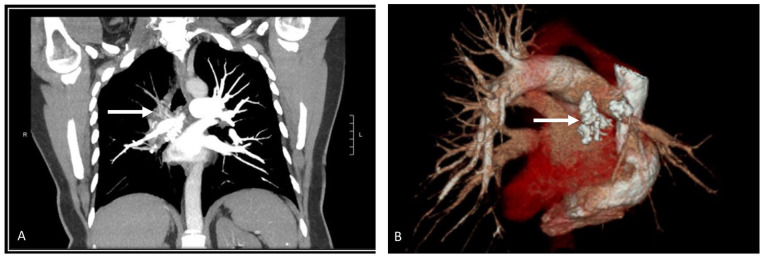

Pulmonary embolism (PE) poses a significant health risk in the United States, with high mortality rates. Clinicians maintain a low threshold for suspecting PE, potentially leading to deviation from guideline-recommended algorithms and unnecessary computed tomography pulmonary angiography (CTPA). This case discusses a 46-year-old woman who presented with symptoms suggestive of PE following a prolonged road trip. Despite a low Wells score and negative D-dimer results, she underwent CTPA, resulting in an unnecessary and harmful interventional radiology-guided thrombectomy. This highlights the importance of adhering to guidelines in PE diagnosis to mitigate potential harms associated with the overuse of available medical tools.